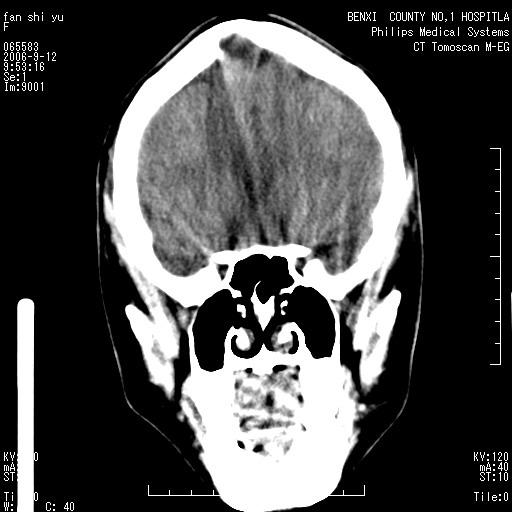

标题: CT4607:看看这个头颅冠状位。

女,22岁,自觉头顶部质硬包块.

巨大蛛网膜粒压迹。

巨大蛛网膜粒压迹